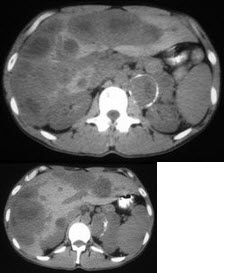

男,37岁,阵发性高血压1月余,请结合所提供图像,选择最佳答案( )

A:左侧肾上腺癌

B:左侧恶性嗜铬细胞瘤

C:左侧肾上腺转移瘤

D:肝转移瘤

E:原发性肝癌